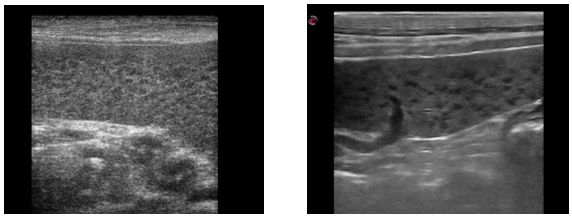

The spleen showed a honey-comb pattern in two dogs (Figure 2) and a heterogeneous structure with multiple iso/hyperechoic focal lesions in one.

Figure 2 (a, b): The honey-comb appearance of the spleen in two dogs with leishmaniasis.

Worth of note is the ultrasonographic honeycomb appearance of the spleen, characterized by multiple small hypoechoic nodules, that is suggestive of lymphoma or lymph sarcoma [16] or pyogranulomatous splenitis in dogs [16]. It was never been previously associated specifically with CVL. In this study the microscopic examination of multiple spleen fine needle aspirates revealed the presence of amastigotes of Leishmania spp. and the resolution of US changes after specific treatment confirmed the association with the infection (or reaction to the infection). In human medicine, Saxena and colleagues [17] observed a similar sonographic appearance of the spleen in a 7-year-old girl with leishmaniasis.